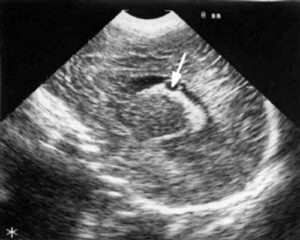

На изображении должны четко просматриваться все анатомические структуры. Костные элементы гиперэхогенны (белые). Сама мозговая ткань имеет среднюю эхогенность (серая окраска). Важным элементом является межполушарное пространство. На нейросонографии оно выглядит как гиперэхогенная полоска, имеющая бороздки.

У ребенка любого возраста на УЗИ должно визуализироваться мозолистое тело. Оно представлено совокупностью нервных волокон, которые поддерживают связь симметричных отделов между собой. Также необходимо оценить состояние ликворной системы, которая состоит из желудочков и цистерн. Они выглядят в виде анэхогенных (черных) полостей, заполненных жидкостью.

- Гидроцефалия. Это состояние характеризуется избыточным накоплением жидкости в черепной полости. При исследовании можно увидеть расширенные и бесформенные желудочки и цистерны, заполненные черной (гипоэхогенной) жидкостью. Также изменяется подпаутинное пространство. Оно приобретает вид утолщенной черной полоски.

- Порэнцефалия – порок развития, при котором в средних отделах полушария обнаруживаются полости. На нейросонографии они проявляются в виде овальных теней с четкими границами.

- Опухоли. Если новообразование располагается в центральных отделах, то возможно возникновение смещения структур мозга. Также к признакам опухолей относят кальцификаты, кровоизлияния и кисты. На НСГ можно увидеть округлые тени с четкими или нечеткими (в зависимости от вида) контурами. Эхогенность образований также может варьировать. Вокруг образования нередко обнаруживается воспалительный вал, который отличается от нормальных тканей повышением эхогенности (светлее здоровых участков).

Такие кисты называют новообразованиями сосудистых сплетений, они визуализируются в заднем роге правого бокового желудочка как образования с четкими ровными краями. Новообразования не вызывают нарушений динамики ликвора и увеличения внеклеточного пространства.